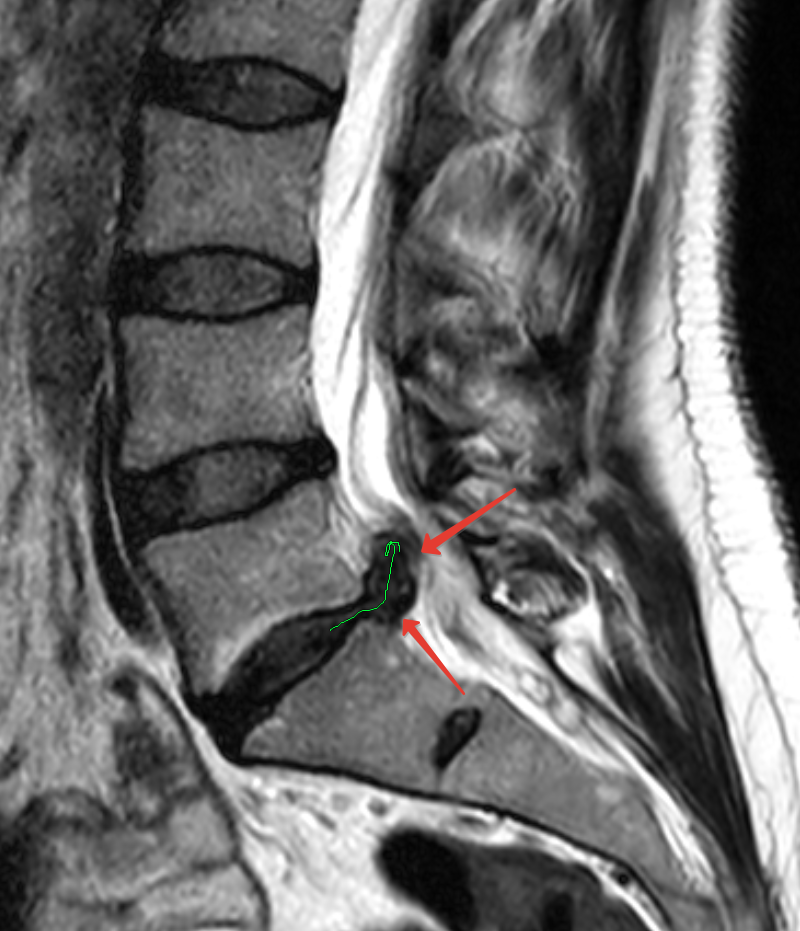

Межпозвонковый диск — это “амортизатор” между позвонками. Он состоит из более мягкого внутреннего содержимого и плотного внешнего фиброзного кольца. При протрузии диск выпячивается, но наружная оболочка еще не разо…